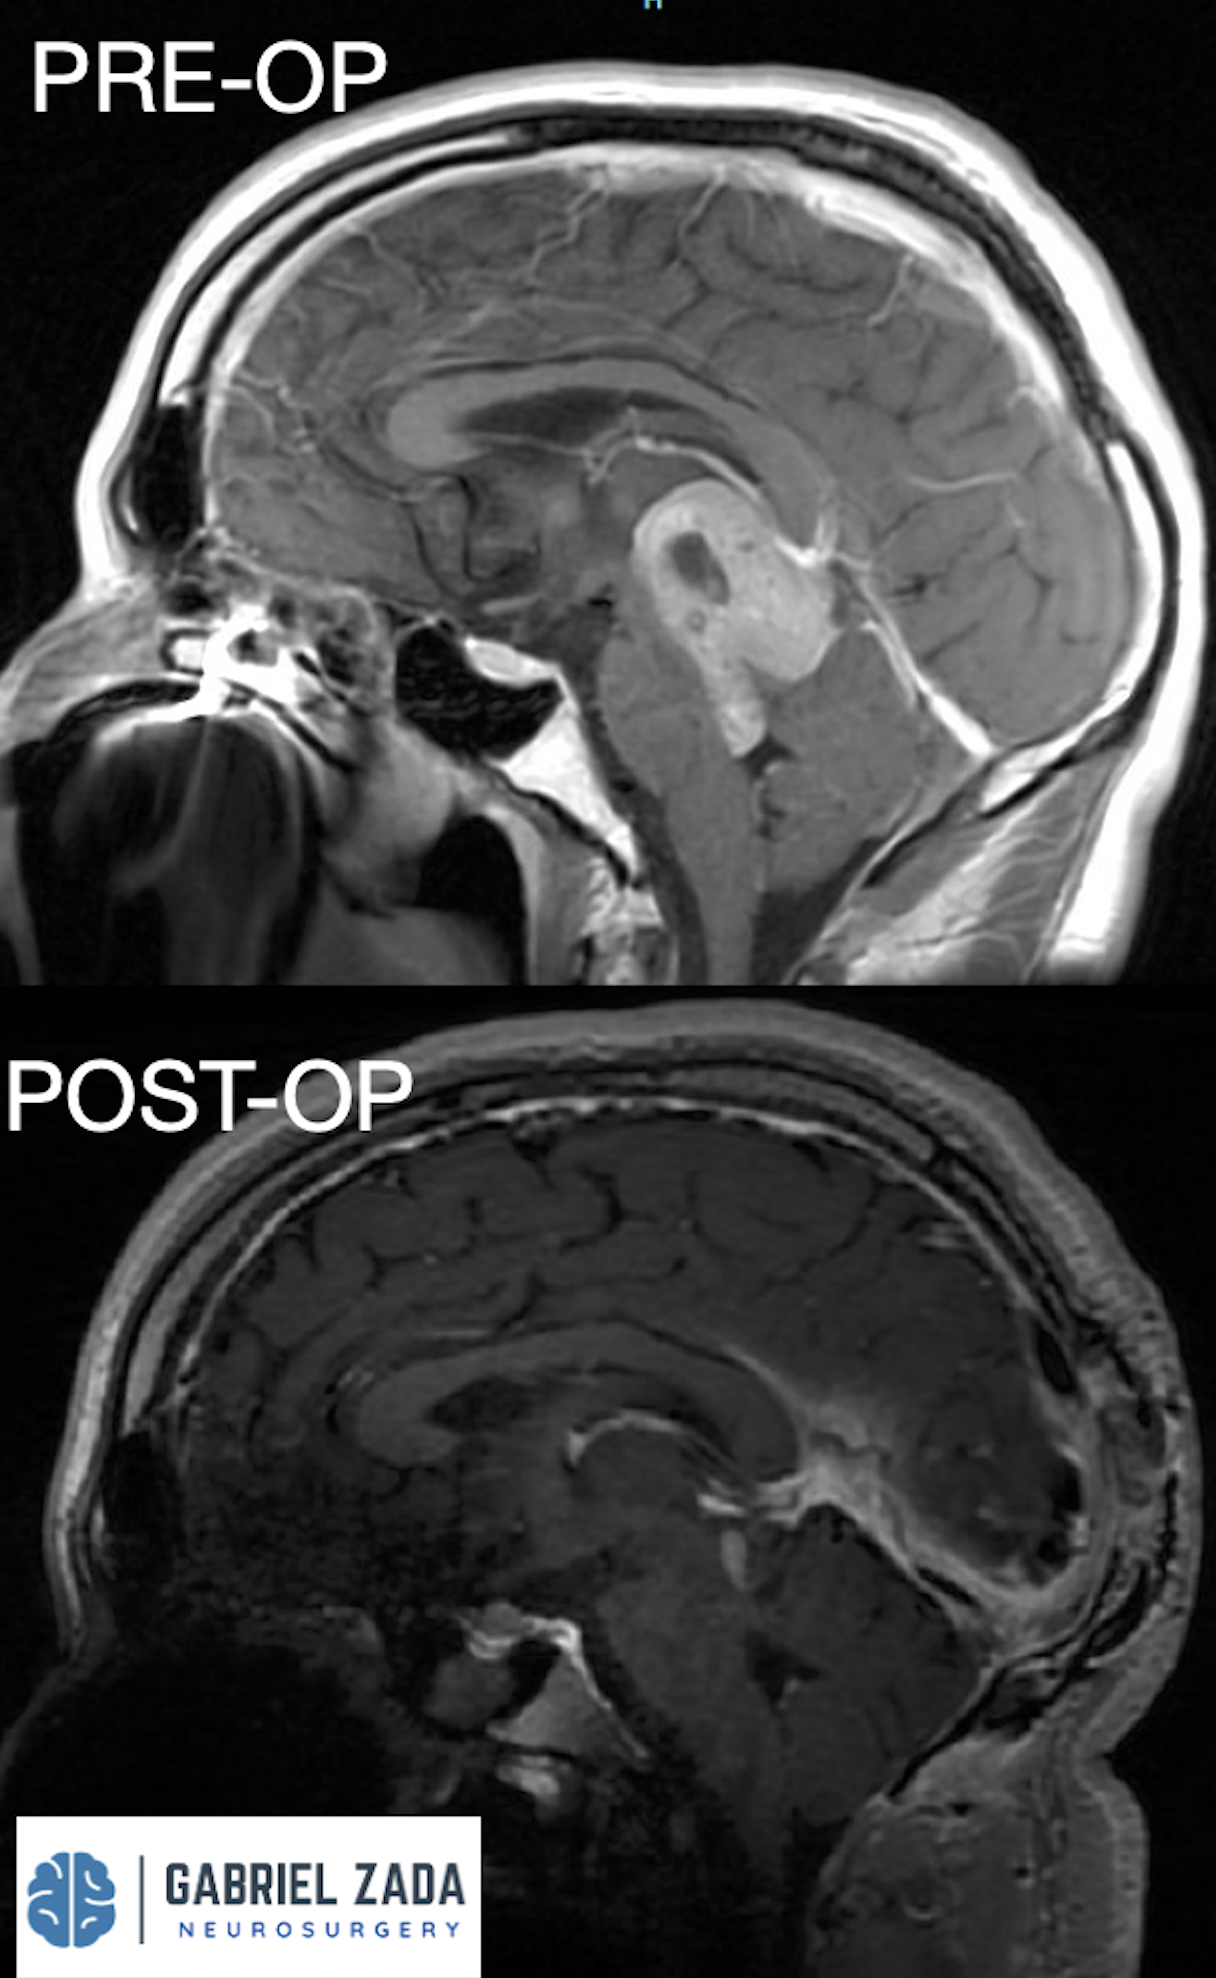

Explore this comprehensive gallery featuring pre‑ and post‑operative imaging of patients with skull‑base tumors treated by Gabriel Zada, MD, MS, FAANS, FACS. These cases highlight Dr. Zada’s expertise in advanced neurosurgical techniques and outcomes.

*Representative cases shown for educational purposes. All images de-identified. Individual results vary.